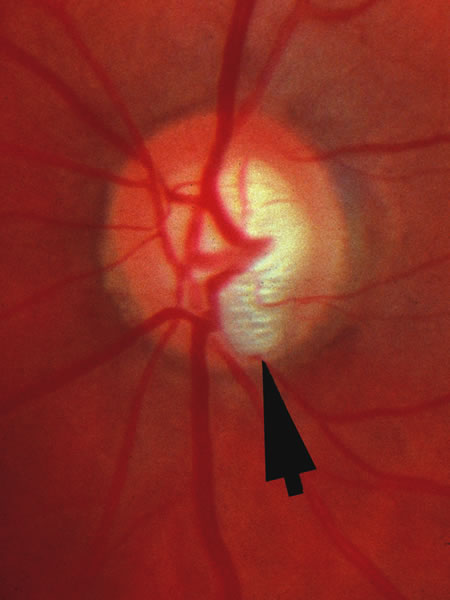

Fig. 31. Advanced glaucomatous cup with complete loss of tissue at the upper and lower poles of the disc, a splinter hemorrhage nasally, and a glaucomatous halo of atrophic choroid and retinal pigment epithelium. The disc itself is separated from the peripapillary β zone by a conspicuous white stripe of the scleral lip.

Fig. 32. An obviously glaucomatous disc with particular loss of tissue in the inferior and superior sectors. A splinter hemorrhage among the axons crossing the disc margin is present at the 4:30 meridian. Typical glaucomatous hemorrhages are elongated and usually extend from the disc tissue across the disc margin somewhat into retina. They may overlie an adjacent peripapillary zone of choroidal or pigment epithelial atrophy, but usually have at least one end touching the disc margin. Nonglaucomatous hemorrhages are usually obvious in context of diabetic retinopathy, retinal vein occlusion, papillitis, etc.